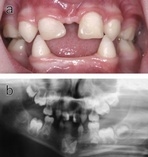

Hair may be sparse and brittle and slow growing. Facial features may be broadened and odd. Ears may be malformed. The eyes may have cataracts giving them a cloudy appearance. Fingernails may be thick and brittle. People affected by this condition also have less sweat glands and therefore cannot tolerate heat. One of the most attention-drawing features of this condition is how it affects the teeth. Teeth may be missing and/or pointed and fang-like with prominent canines.